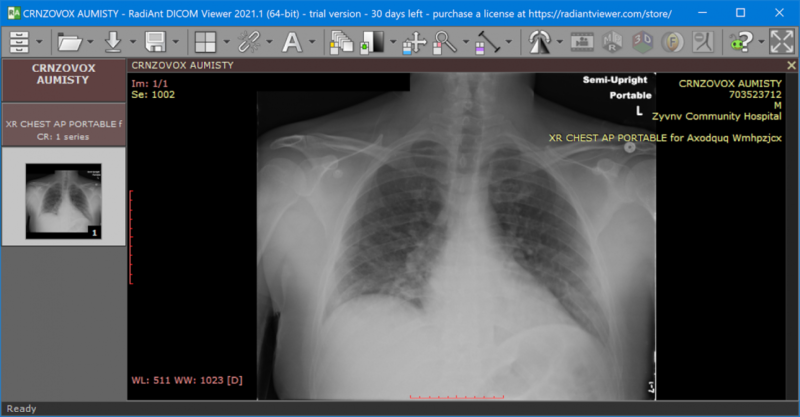

DICOM (Digital Imaging and Communications in Medicine)

- The standard format for medical imaging worldwide

- Contains both pixel data AND rich metadata

- Metadata includes: patient info (ID, demographics), acquisition parameters (modality, equipment), organizational hierarchy (study, series, instance)

- Used by CT, MRI, X-ray, ultrasound, PET, and more

pydicom: Specialized for DICOM files — read/write medical images and access rich metadata (patient info, acquisition parameters, modality).